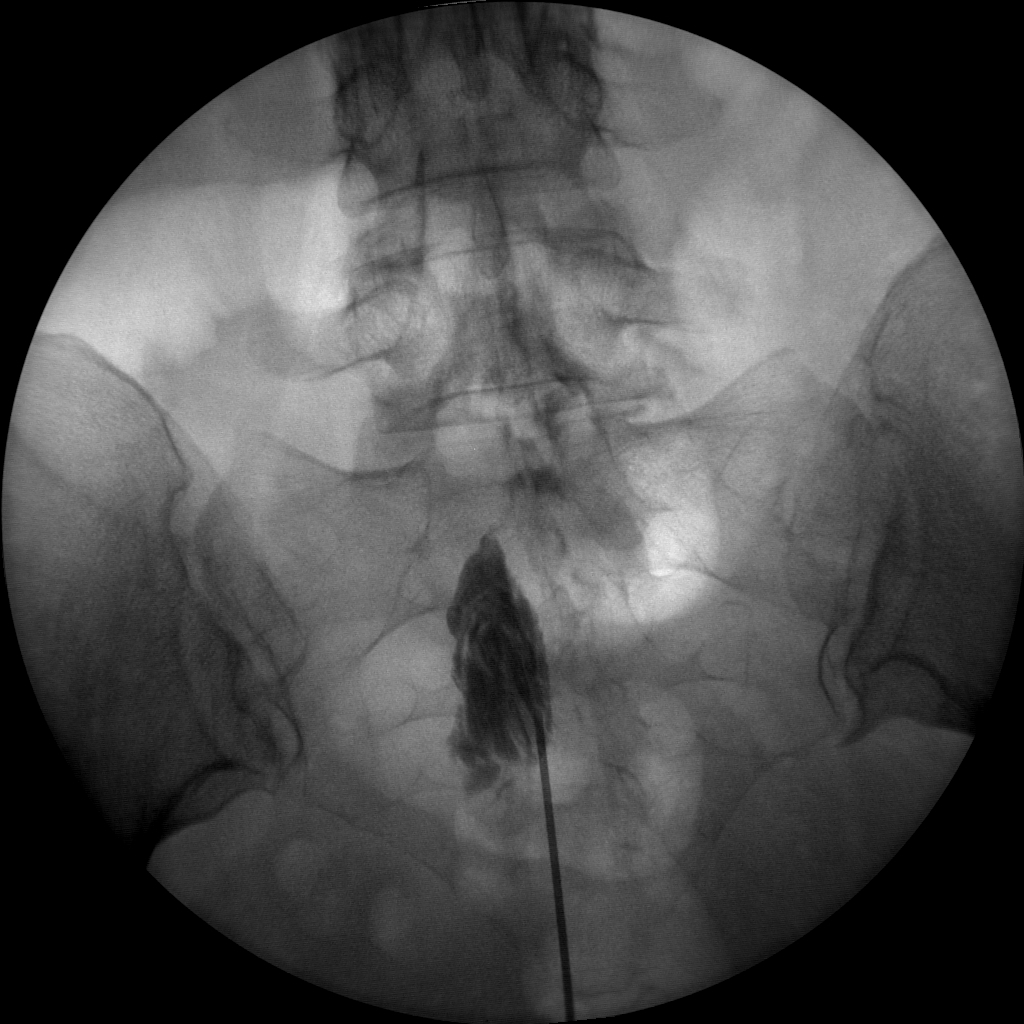

Versatility

Skan-C is a highly versatile machine that can be used for a variety of pain management treatments, including epidural injections, nerve blocks, joint injections, and more.

High-quality imaging

Skan-C uses advanced imaging technology, such as pulsed fluoroscopy and digital subtraction angiography, to provide highly detailed images of the affected area. This allows doctors to perform procedures with increased precision and accuracy, and better patient outcome